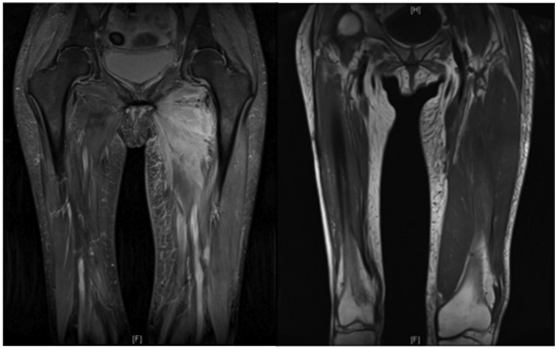

Her diabetes was poorly controlled on insulin, with her most recent HBA1c being 84 mmol/mol (21-42 mmol/mol). She had a normal White cell count with CRP of 159.1 mg/L (<5 mg/L) and CK 426 IU/L (<150 IU/L). A Doppler scan was negative for DVT and MRI (Figures 1 & 2) showed left thigh muscle oedema and necrosis affecting the anterior compartment. A possibility of pyomyonecrosis was suggested. To rule out the same, an ultrasound guided biopsy was performed. The aspirate revealed no growth from microbiology and histology revealed fiber atrophy, very few macrophages in the perimyosial connective tissue, and more importantly, thickened and hyalinised walls of small endomyosial and perimyosial capillaries with evidence of necrotic fibers. These findings are highly suggestive of necrotizing myopathy. With pipestem capillaries and minimal cellular infiltration, the possibility of an infective aetiology was ruled out.

Figure 2 T1 and T2 weighted coronal MRI of the both thigh showing increased signal intensity and muscle edema affecting the anterior compartment of the left thigh.